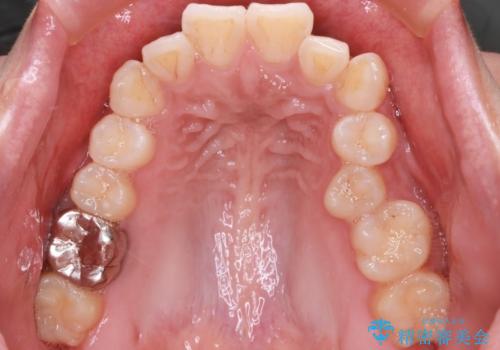

前歯の前突と口元の突出感を改善|上下左右4番抜歯+審美ワイヤー矯正

- 前歯の突出が強く、口元が前に出ている印象を改善するため、上下左右の第一小臼歯(4番)を抜歯する矯正治療を計画しました。抜歯により得られたスペースを利用して、前歯を後方へと移動させて整列します。治療には目立ちにくい透明な審美ブラケットとワイヤーを使用し、毎月1回の調整を行いながら徐々に歯を動かし、約2年で口元全体を整える計画としました。

前歯が前に出ているため口元が突出し、唇が閉じにくいなどの悩みを抱えておられました。治療にあたり上下左右の第一小臼歯を抜歯し、十分なスペースを作ることで前歯を効果的に後方へ移動させました。装置には透明で目立ちにくい審美ブラケットを採用し、治療中の審美的ストレスを軽減しました。定期的な調整を通じて無理なく確実に歯列を整え、前歯の突出感を解消。治療後は口元の印象が自然で美しく改善され、患者様には非常にご満足いただけました。